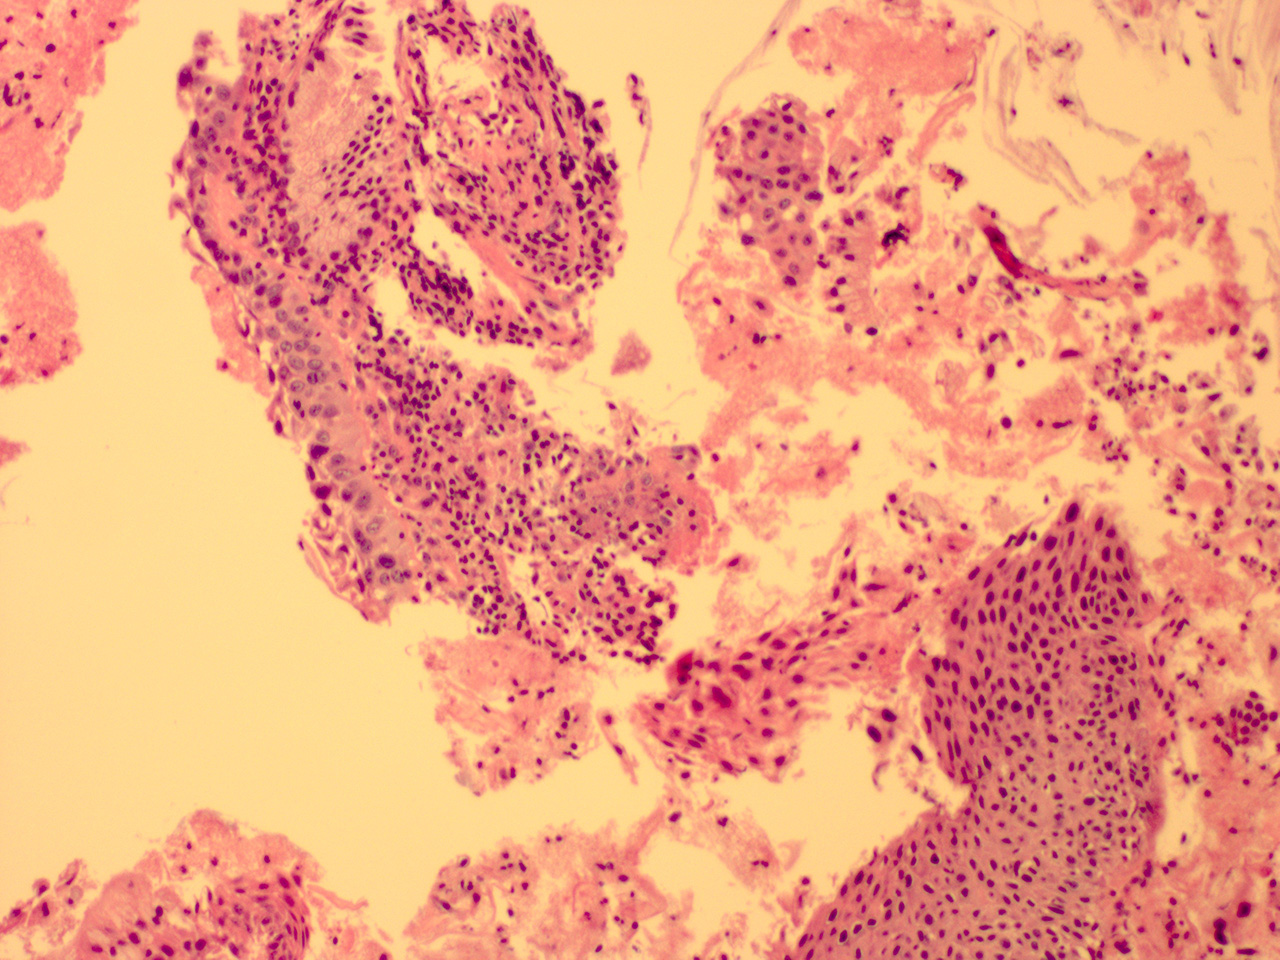

Case 3

Soft Bx CIN 2-3 10x - Low Power

![]() Case 3

Soft Bx CIN 3

10x - Low Power |